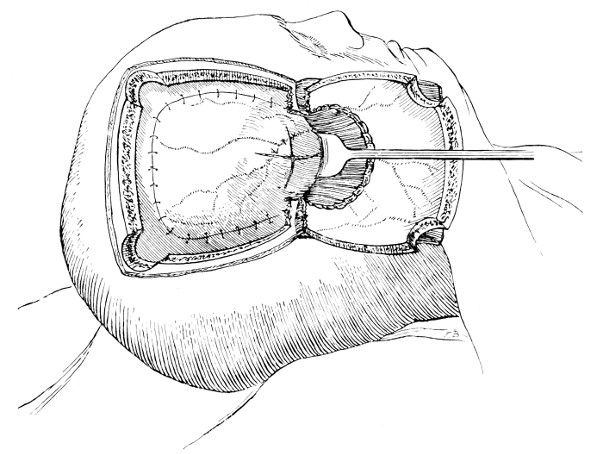

Between these two trephine-holes the dura mater is separated from the bone and the special director introduced, entering at the one hole, emerging at the other, and lying throughout between the dura and the bone. The saw is now passed along the groove of the director, the handles affixed, and the bone intervening between the two trephine-holes divided, not straight out to the surface, but bevelled or cut in such an oblique manner that the bone-flap, when replaced, rests on a ledge (see Figs. 17-19). The sawing process[26] generates considerable heat, and the assistant should be instructed to keep up irrigation with saline solution or sterilized water. The sawing is carried out by steady side-to-side traction, without jerks; if the saw breaks, the special handle may be attached, thus obviating the necessity of introducing a new saw.

The dura is now separated from the bone along the line of the two vertical incisions, and the visceral blade of de Vilbiss’s forceps insinuated beneath the bone, starting at one trephine-hole and working downwards to the lower limit of the incision. It is essential that the operator should be satisfied with the ‘morcellement’ of small portions of bone at each bite of the instrument. At the lower end of each[28] of the vertical incisions the forceps is directed inwards for 1⁄4 to 1⁄2 inch so as to weaken the base of the flap.

To lift up the osteoplastic flap, a stout elevator or spatula is introduced beneath the bone at its upper part, leverage applied, and, as soon as sufficient elevation has been attained, the dura mater carefully separated from the whole of the under aspect of the flap. The flap is then grasped at its upper part with both hands and, with a quick but forcible jerk, broken across at its base, the assistant at the same time aiding the correct linear fracture of the bone by a flat spatula applied to the outer aspect of the base of the flap. Insomuch as the flap is most usually framed in the parieto-temporal region—for the exposure of the motor area—the base of the flap, being formed from the squamous portion of the temporal bone, is comparatively weak. Fracture is then readily obtained. Under other circumstances the base may be sufficiently weakened by the application of the de Vilbiss forceps or by the use of the Gigli saw.

The bone-flap is thrown back and enveloped in gauze. Its basal region is examined for a possible injury to meningeal vessels. In the event of such complications the bleeding vessel is clipped, ligatured, or underrun. Possibly some branch of the anterior division of the middle meningeal artery, running in an osseous canal, may require to be controlled by foraminal occlusion—with a wooden match, bone peg, cotton-wool, or aseptic wax.

In comparing the relative advantages and disadvantages of craniectomy and craniotomy, although there are certain definite contra-indications to the latter method, yet craniotomy should always be carried out when the surgeon desires to expose a large surface area of brain, more especially in the exposure of a tumour diagnosed to lie in relation to the motor cortex. Even if the operator should be unsuccessful in his exploration, or, if finding the tumour, should deem it irremovable, the dura can be sewn up and the bone-flap replaced, resting on its bevelled edge, with little defect in the skull and a normal surface contour.

The three main disadvantages to craniotomy are as follows:—(1) the operation can seldom be done under much less than thirty minutes; (2) there is some slight risk of complication through injury to the middle meningeal artery; and (3) the dura mater may be so[29] adherent to the bone as to be torn in the process of flap-elevation. Time, however, is usually of little importance; bleeding from the middle meningeal artery may be controlled, and dural lesions may be avoided by careful technique. In general, the advantages of osteoplastic resection greatly outweigh the disadvantages.